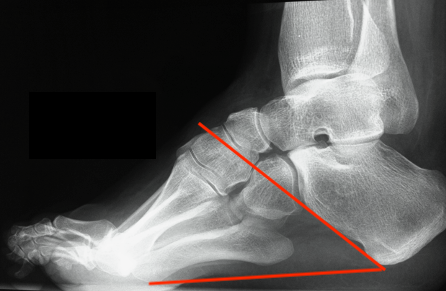

Calcaneal Pitch

- normal 20o or less

- > 30o abnormal